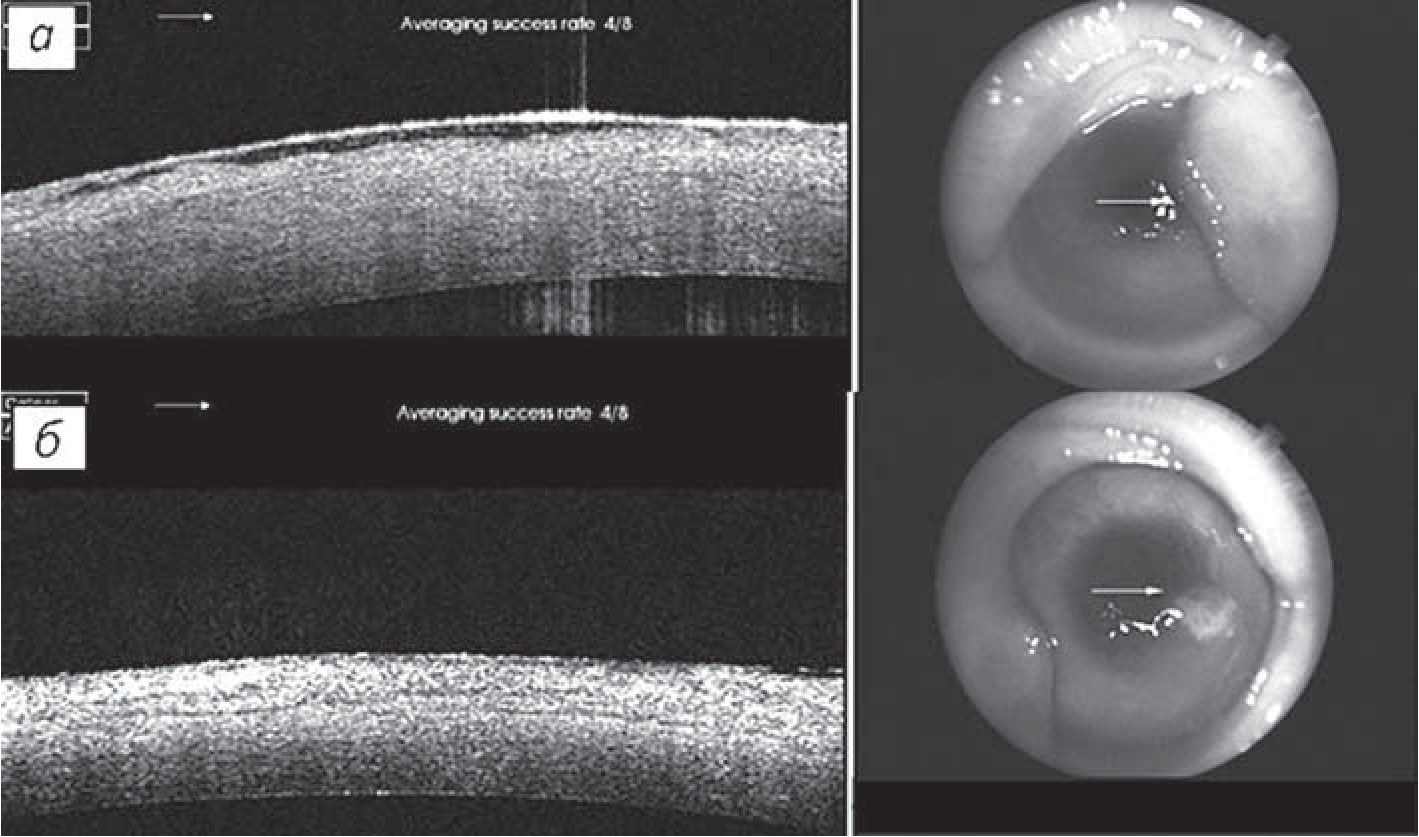

В зависимости от способа фиксации АМ было сформировано две экспериментальные группы: А – контрольная (6 глаз) – фиксация узловыми швами, Б – основная (6 глаз) – фиксация ФК. Более раннее начало эпителизации роговицы отмечено в основной группе на 5-е сутки, в группе контроля – на 7-е сутки, но полная эпителизация роговицы наступила раньше в контрольной группе (на 21-е сутки) в связи с тем, что в ней наблюдался выраженный лизис АМ начиная с 7-х суток после операции. По данным биомикроскопического обследования на 90-е сутки (рис. 2), прозрачность роговицы в группе Б была значительно выше, чем в группе А, неоваскуляризация в обеих группах доходила до оптической зоны роговицы, но в основной группе плотность сосудов была значительно ниже.

Рис. 2. Фоторегистрация прозрачности роговицы на 90-е сутки: а – группа А; б – группа Б

По данным сравнительной оптической когерентной томографии (рис. 3) выявлено, что в группе А эпителий в центральных отделах неадгезирован, визуализируются субэпителиальные кисты, АМ присутствует только в параоптической области и постепенно истончается до полного исчезновения в оптической зоне. В группе Б АМ интегрирована на всем протяжении, эпителий полностью адгезирован, субэпителиальные кисты отсутствуют.

Рис. 3. Сравнительная оптическая когерентная томография на 30-е сутки эксперимента: а – контрольная группа; б – основная группа